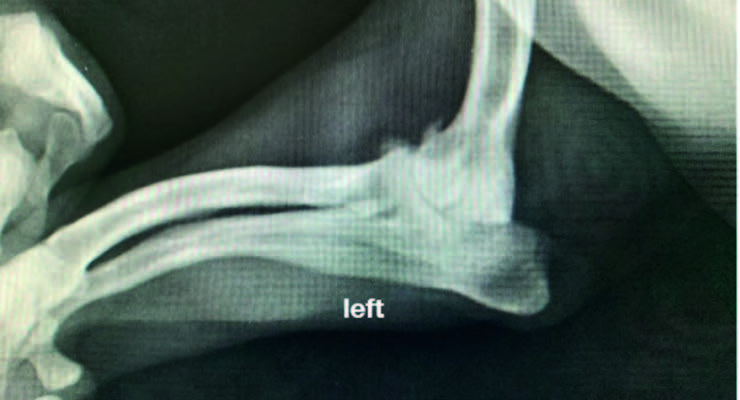

An analysis was conducted on a representative sample of ten dogs afflicted with OA, which were subjected to magnetotherapy treatments, two sessions per weeks, for a duration of six weeks. The principal indicators of interest included the degree of pain on palpation and the degree of lameness, joint mobility, muscle circumference and the dogs’ level of participation and happiness.